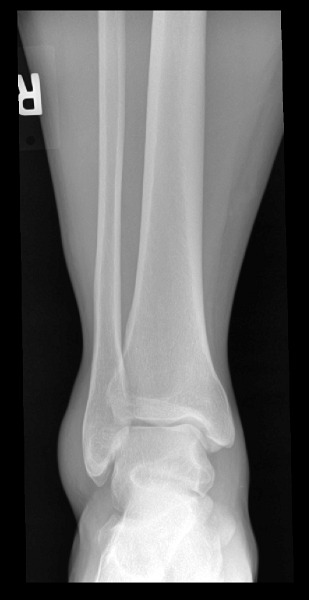

Ankle (1) Ankle (1) Ankle (2) Ankle (2) Ankle (3) Ankle (3)

Ankle (4) Ankle (4) Ankle (5)